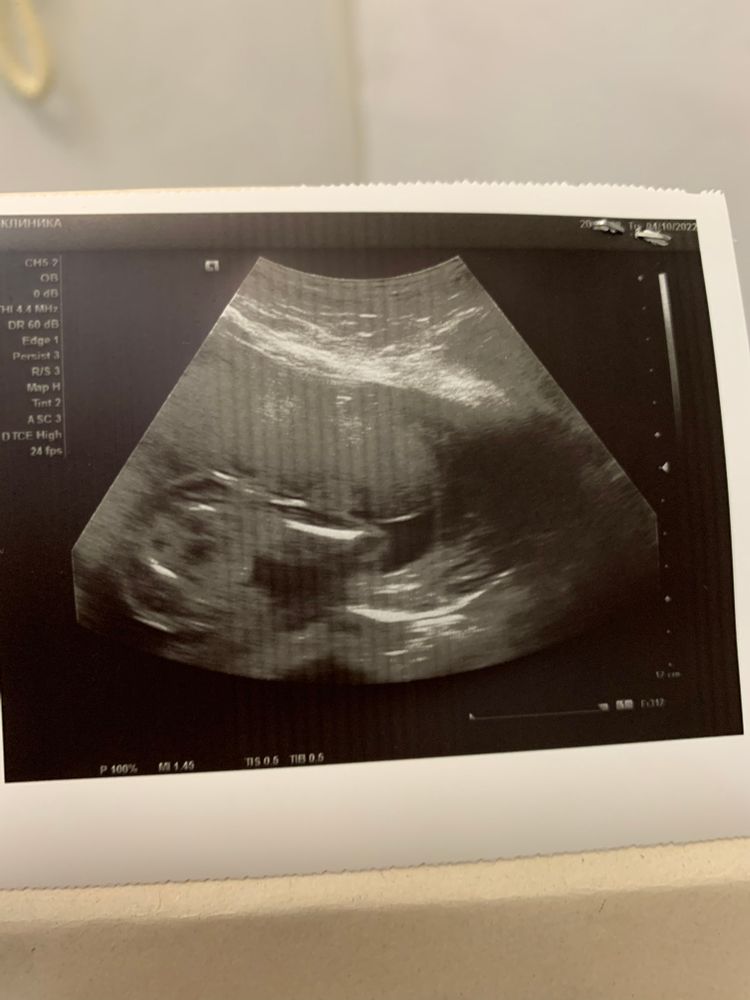

Экспертное узи

Пол малышаЕду от врача. Узнала пол. Мне надо это переварить. Анекдот прям про меня.